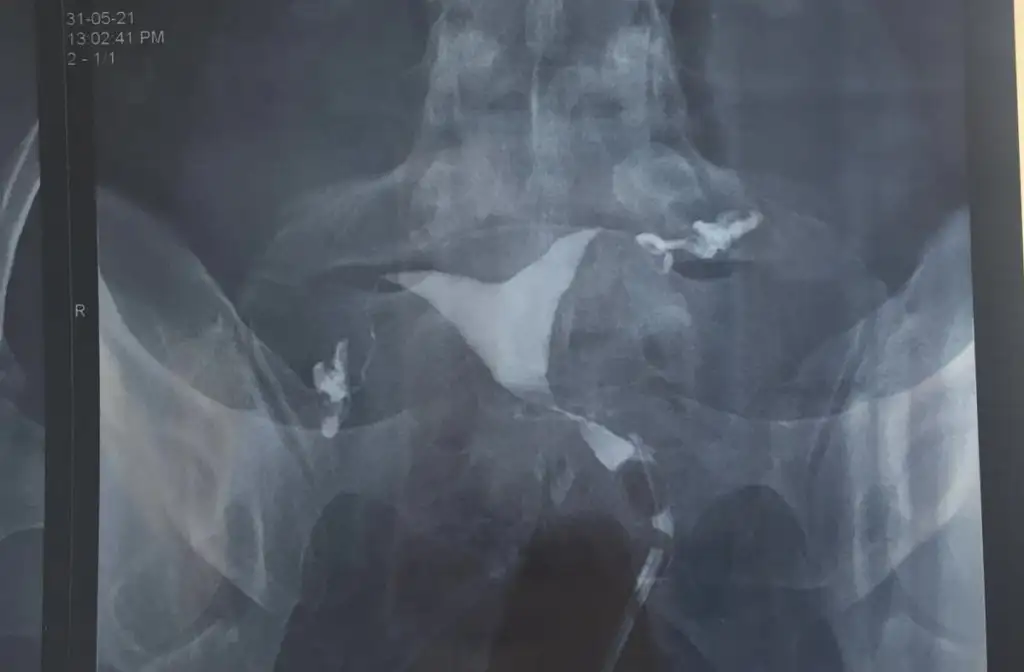

Y Rahime nasıl sorun yok dedi harbiden? 2 düşük yaptığım için hsg çektirdim sonuç bu.Y rahime sorun yok mu dedi?

Geçmiş olsun. Histerekopi ile hallolur insallah sorun. Genetik testlerinizi de yaptırdınız mı?Y Rahime nasıl sorun yok dedi harbiden? 2 düşük yaptığım için hsg çektirdim sonuç bu.

Teşekkür ederim canım. Evet herşeyi yaptırdım onlara sorun yok dedi en son hsg çekildim Y rahim çıktı dediğiniz gibi histerekobi olmam gerektiğini söylediGeçmiş olsun. Histerekopi ile hallolur insallah sorun. Genetik testlerinizi de yaptırdınız mı?

Iyi iyi temiz çıktılarsa.Teşekkür ederim canım. Evet herşeyi yaptırdım onlara sorun yok dedi en son hsg çekildim Y rahim çıktı dediğiniz gibi histerekobi olmam gerektiğini söyledi